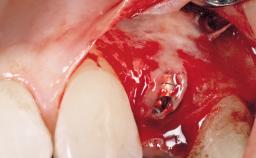

A 33-year-old female patient presented with an upper left central incisor that required extraction after a failed endodontic therapy. The tooth had been traumatized when the patient was a teenager and had undergone several endodontic treatments, including two apicectomy procedures. The patient was in good health and did not smoke. Clinical examination showed that the patient had a high lip line. In full smile, the gingival margins of the upper teeth were visible to the first molars. The gingival margins of central incisors 11 and 21 were only just showing. Examination of tooth 21 confirmed that the tooth was mobile and had hypererupted by 1 mm.

Placement Protocol Immediate implant placement

Socket Morphology Single-root socket

Socket Integrity Damage to one or more bone walls

Bone Volume Damage to one or more socket walls